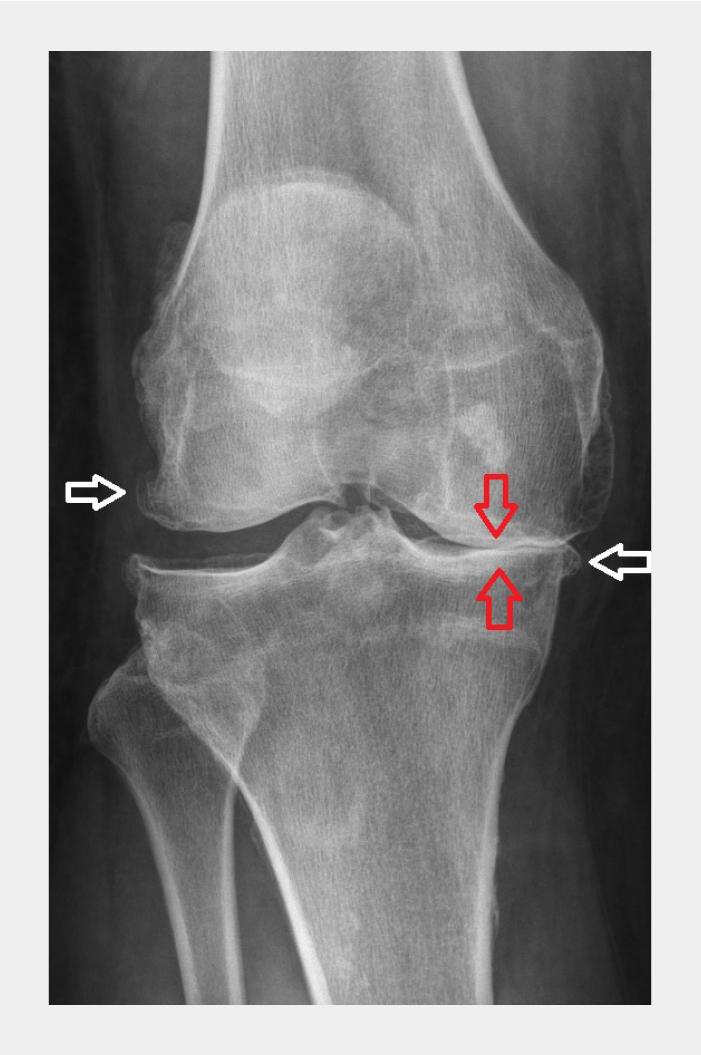

Als een röntgenfoto gemaakt wordt, zijn bij aanwezigheid van artrose de volgende kenmerken te zien: asymmetrische gewrichtsspleetversmalling, subchondrale botvorming, cysten, osteofyten en subluxatie van het gewricht (figuur 3 en 4).

Figuur 4

Anterieur-posterieure röntgenopname van rechter knie met gonartrose

Figuur 4 | Anterieur-posterieure röntgenopname van rechter knie met gonartrose

De witte pijlen tonen osteofyten en de rode pijlen de gewrichtsspleetversmalling.